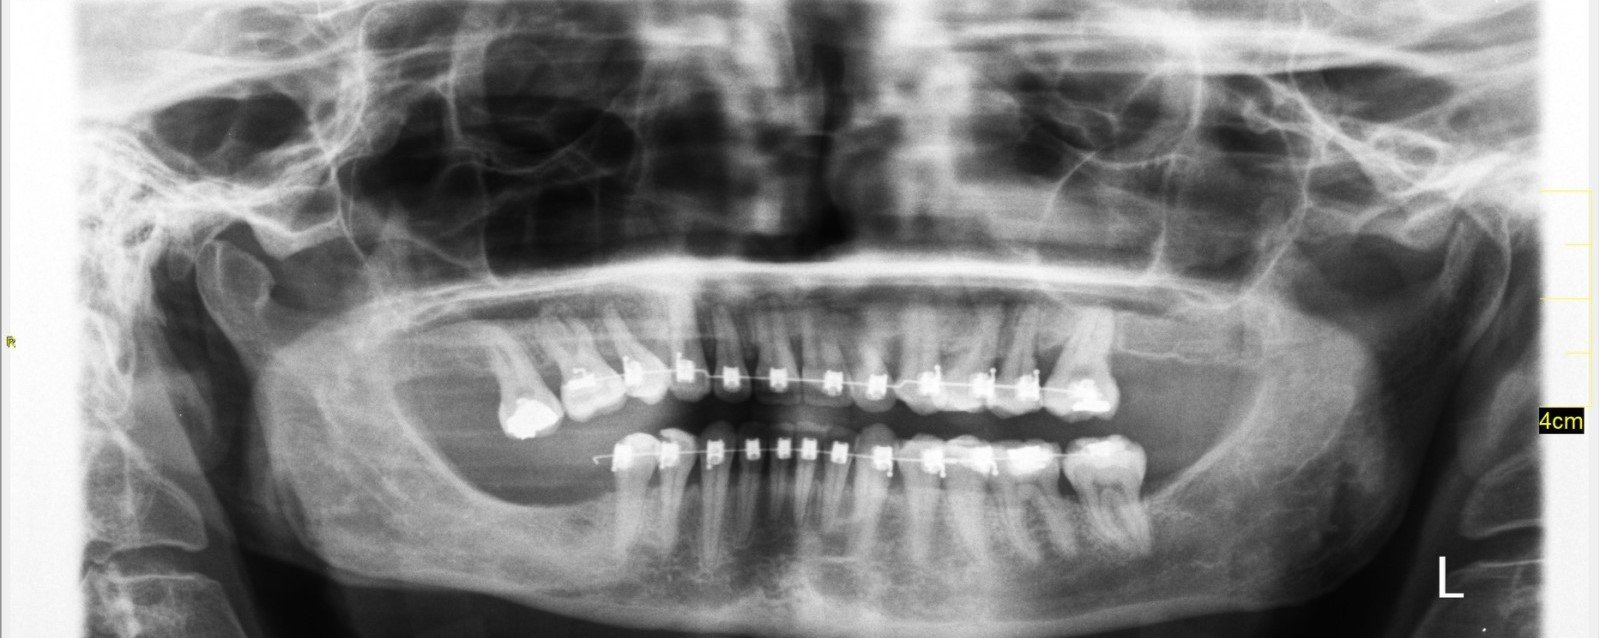

Здравейте, две години нося брекети, скоро ще ги махам, но през това време са настъпили и неприятни последствия. Прилагам снимка, разбрах, че не е много добра, за което се извинявам, но ще помоля за мнение. С какво да се захващам след като ги сваля?

Скрит текст:

Да, за съжаление, явно на парче лекуват някои. Но късно го разбрах. В провинцията съм, ако има значение, но явно тук е така. Един ти прави нещо и после казва да си търсиш някой да оправя. Един ми беше в младежките години, според който 10 години всичко беше наред, докато не потърсих 2ро мнение и разбрах, че все едно съм била немърлива, а аз не съм. Той е бил. Та сега, ортодонтът е към края на лечението си и каза да си търся някой друг за другите неща, които са се появили. До имплант не съм стигнала, трябваше първо брекети. Поне така ме посъветваха. Искам да разбера имам ли загуба на кост и джобове.

Имаш..по мое скромно пациентско мнение. И джобове и стопена кост...

teta75 тук има ли стопена кост

Не съм зъболекар..но има стопена според мен.

Черните триъгълници са липса на кост